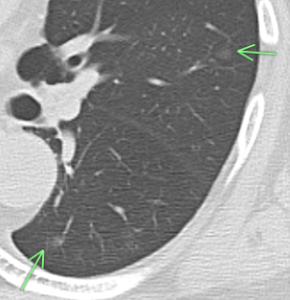

83歳 男性 両肺に多数のすりガラス結節あり(緑矢印)

(症例1)典型的な肺内リンパ節

4.96㎜大の充実性多角形の小結節で、胸膜との間に線状影あり(緑矢印)。

(症例2)増大した肺内リンパ節

X年 X+9年

充実性多角形の線状影を伴う結節ですが、9年の経過で増大したので切除された。

結果は肺内リンパ節であった。